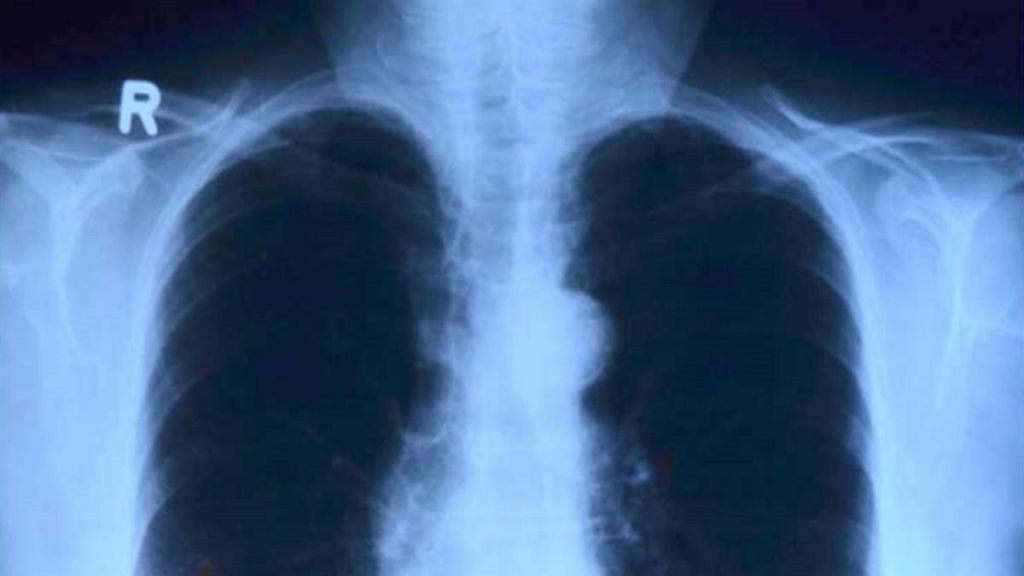

El ministro de Salud Pública de Tucumán, Luis Medina Ruiz, informó el martes en una rueda de prensa que se desconoce la causa de esta dolencia que produce cuadros de neumonía bilateral, sin que se sepa aún si es de origen viral o bacteriana.

El titular de Salud Pública provincial informó que se detectó un brote de neumonía bilateral en seis pacientes, cinco de ellos trabajadores de la salud.

El fallecido era un galeno de la clínica Luz Médica que presentaba un cuadro respiratorio derivado de una neumonía bilateral. En ese centro de salud privado, ubicado en San Miguel de Tucumán, se detectó inicialmente el brote, según La Gaceta. En el sanatorio se ordenaron medidas preventivas. Las autoridades decidieron no cerrar el lugar, pero sí aislarlo de forma temporal. Además, restringieron el ingreso de nuevos pacientes, las consultas internas y las visitas.